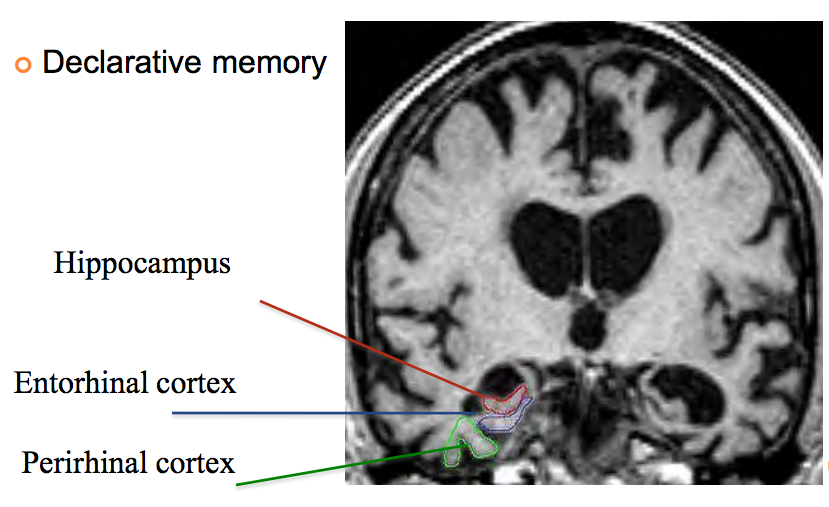

Describe the main system in the brain that is important for memory?

Hippocampal system

Hippocampus, entorhinal cortex, perirhinal cortex